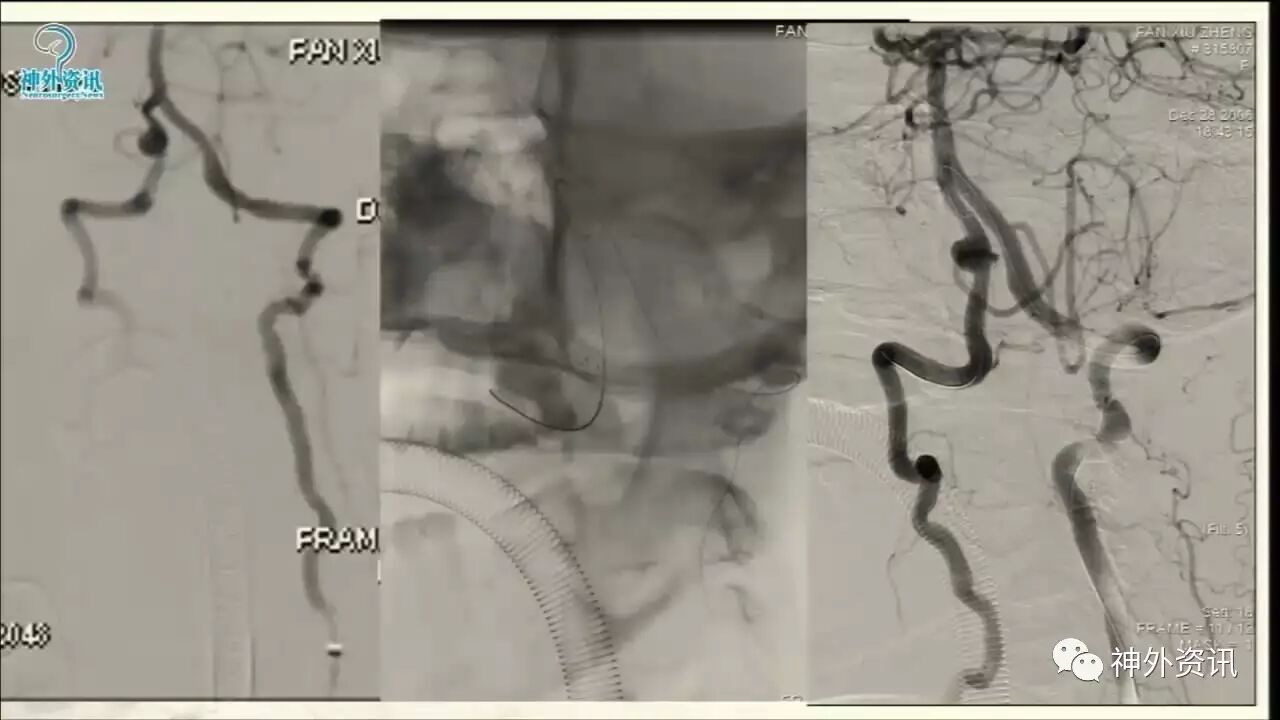

今天“神经介入专栏”为大家分享由上海交通大学医学院附属仁济医院神经外科副主任万杰清教授带来的“颅内小动脉瘤的介入治疗--GALAXY微弹簧圈是一种不错的选择”精彩讲课视频及PPT,欢迎观看、阅读。文章仅代表作者个人观点,如有不同见解,欢迎同道斧正!